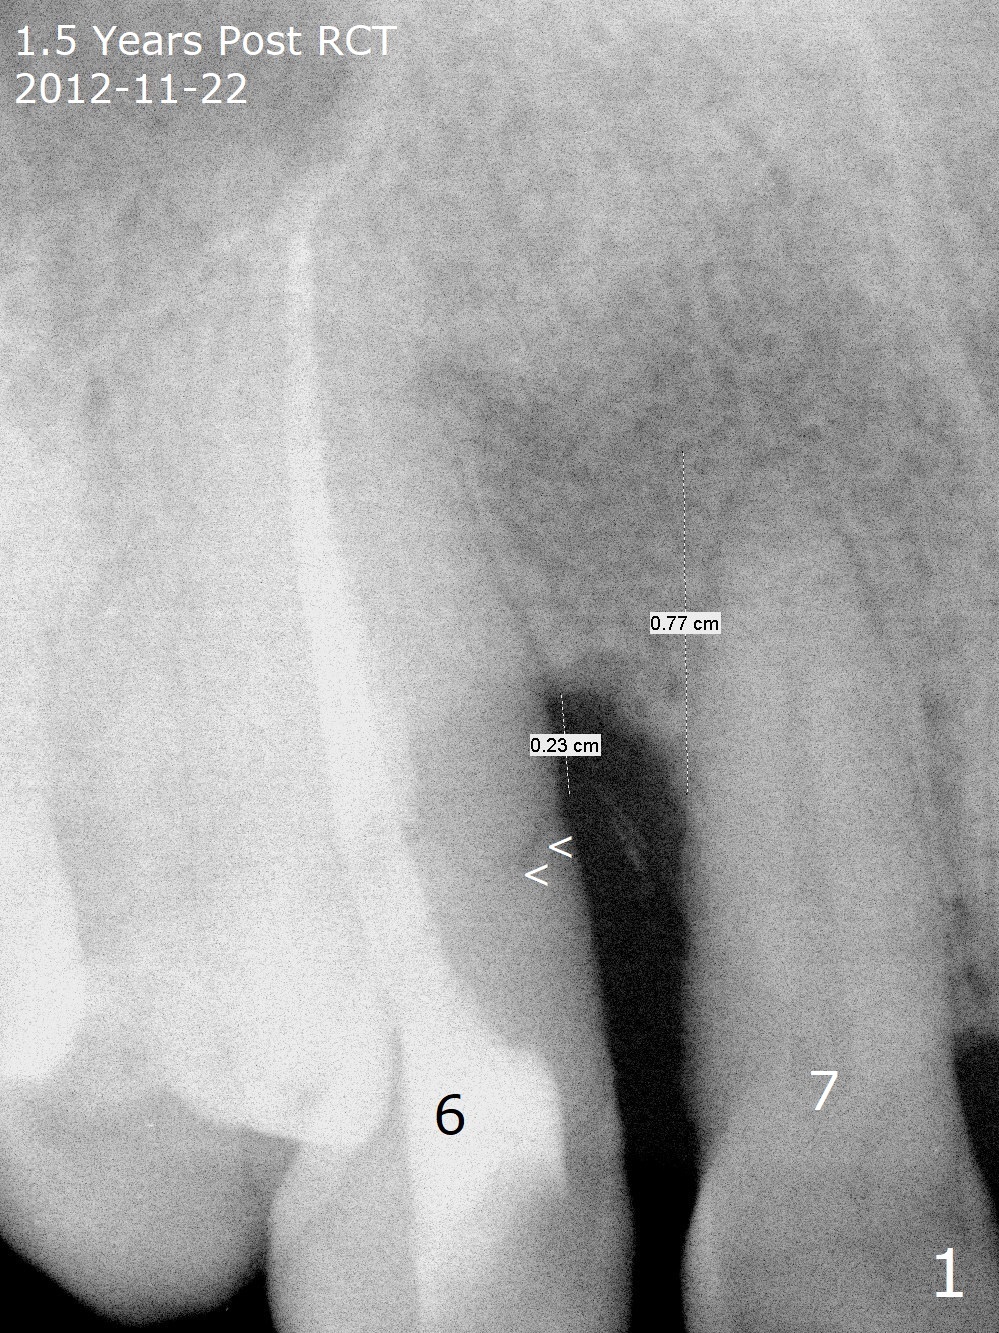

A 62-year-old man had traumatic root fracture at #6 in his teen. The tooth remained asymptomatic until his fifties. Following root canal therapy (Fig.1), the tooth is orthodontically extruded (~ 5 years, Fig.2 (*: bracket)) with apparent disappearance of the infection. The bone distal to #7 seems to increase in height (Fig.3, as compared to Fig.1) and in density (Fig.4). Bone graft could be placed for regeneration with PRF or GEM21S (Fig.5 red (between #6 and 7), pink (buccal to #7 or coronal to the fracture line) circles). With extrusion, the oblique fracture line is more than half or two third supragingival (Fig.6). In spite of severe bone loss, exostosis is present (Fig.7 (mesiobuccal view) E) so that bone graft could be placed palatal to it (Fig.8 red). In case the tooth is non-salvageable, immediate implant will be placed with guide (Fig.9,10). Move lingual button as apical as possible (Fig.12) and make occlusal clearance. Continue extrusion until all of the crack is exposed without deep pocket.